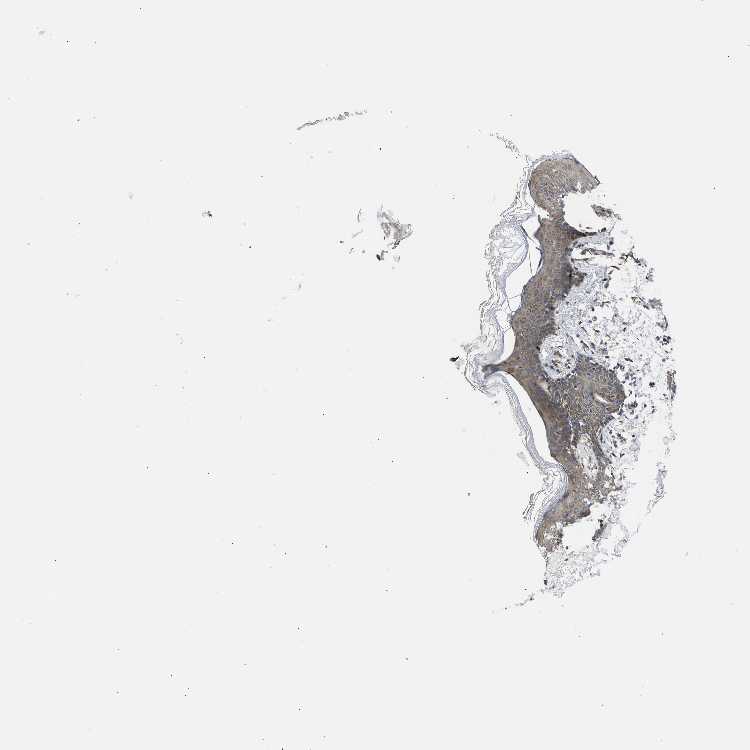

SKIN 1 - Antibody stainingi

Antibody staining in the annotated cell types in the current human tissue is reported as not detected, low, medium, or high, based on conventional immunohistochemistry profiling in selected tissues. This score is based on the combination of the staining intensity and fraction of stained cells.

Each image is clickable and will lead to virtual microscopy that enables deeper exploration of all samples and also displays staining intensity scores, fraction scores and subcellular localization as well as patient and tissue information for each sample.

Antibody HPA024223Antibody CAB015224

Langerhans Not detected-

Cells in basal layer -Medium

Cells in corneal layer -Not detected

Cells in granular layer -Medium

Cells in spinous layer -Medium

Endothelial cells -Medium

Extracellular matrix -Not detected

Fibroblasts Not detected-

Fibrohistiocytic cells -Medium

Keratinocytes Low-

Langerhans cells -Not detected

Lymphocytes -Medium

Melanocytes MediumNot detected

Vascular mural cells -Not detected